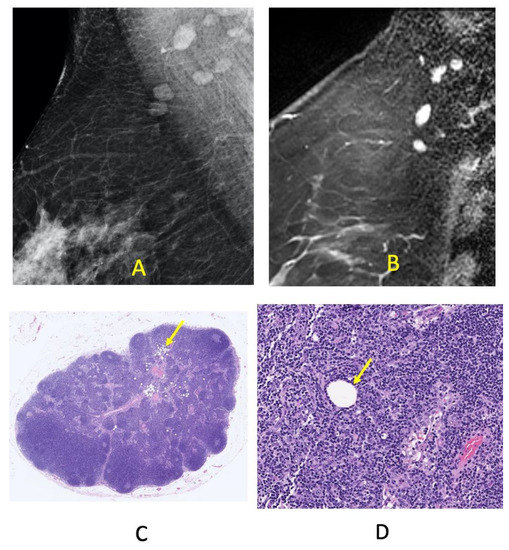

2.2. Methodology